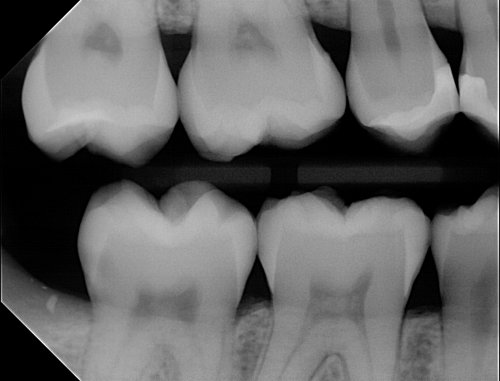

High Resolution CMOS Sensor

With the High Resolution CMOS chip you get crystal clear images in seconds. The Apex Dental Sensors capture high resolution images at 25 Theoretical line pairs per millimeter.

Speed Up Workflow

Digital x-rays appear instantly, providing clinicians with immediate feedback. In an emergency, valuable time is not wasted waiting for film to develop, allowing you to quickly attend to your patient. The Apex Sensor can be conveniently carried to wherever it is needed, from operatory to operatory, for fast, proficient service. With its fast Hi-Speed USB 2.0 connection, you’ll save time every day, no matter the type of appointment.For more Details on the Apex Dental Sensors. Please give our office a call at (800) 869-0915 or Visit DentalSensors.com